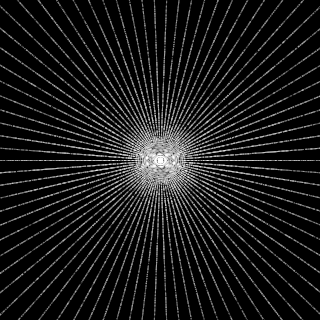

This article presents a novel undersampled magnetic resonance imaging (MRI) technique that leverages the concept of Neural Radiance Field (NeRF). With radial undersampling, the corresponding imaging problem can be reformulated into an image modeling task from sparse-view rendered data; therefore, a high dimensional MR image is obtainable from undersampled $k$-space data by taking advantage of implicit neural representation. A multi-layer perceptron, which is designed to output an image intensity from a spatial coordinate, learns the MR physics-driven rendering relation between given measurement data and desired image. Effective undersampling strategies for high-quality neural representation are investigated. The proposed method serves two benefits: (i) The learning is based fully on single undersampled $k$-space data, not a bunch of measured data and target image sets. It can be used potentially for diagnostic MR imaging, such as fetal MRI, where data acquisition is relatively rare or limited against diversity of clinical images while undersampled reconstruction is highly demanded. (ii) A reconstructed MR image is a scan-specific representation highly adaptive to the given $k$-space measurement. Numerous experiments validate the feasibility and capability of the proposed approach.